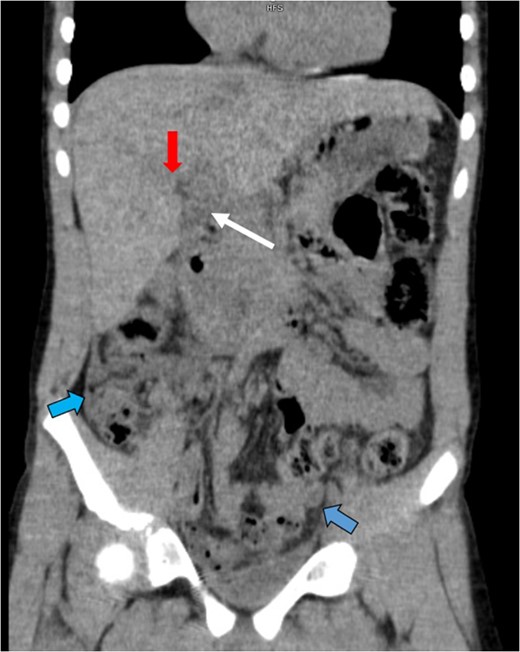

An abdominal CT showed a collapsed gallbladder with wall thickening or pericholecystic fluid (white arrow), a grade II hepatic laceration of Segment 5 (red arrow) and an increased amount of free fluid in the abdomen (blue arrows).